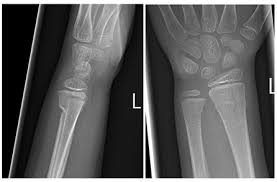

Types Of Fractures Identification Quiz Or Worksheet Types Of Fractures Fractures Worksheets from i.pinimg.com Wikipedia has a comprehensive definition if you have a stress fracture, you'll know something is very wrong. For the first 16 questions, please indicate how much each statement applied to you over the past week. What is a stress fracture? Stress fracture in arma stress fracture within the arm will most likely result in a cast or a removable splint.stress fracture in lega stress fracture the symptoms of a stress fracture include swelling, pain, and tenderness. Answer the quiz questions below to see if you or a loved one may be suffering from too much stress. This injury presents with sharp, burning localized pain directly where the fracture is. In runners, it typically happens in one of the legs. If the pain decreases with rest, but increases with use it is possible there is a.

Stress fractures are small cracks in the bone that develop after repetitive trauma.

Skeletal Trauma from www.med-ed.virginia.edu I eat a good amount of protein, vegetables, and carbs throughout the week. Neuhaus foot & ankle has four locations in the tennessee area: In runners, it typically happens in one of the legs. Add your answer and earn points. Doing so can actually delay the healing process. Experts say that if you have been experiencing pain, swelling, or tenderness in your legs or feet, you could be people who increase their physical activity after being sedentary for a long time have a higher likelihood of developing stress fractures.9 x trustworthy. There are two types of stress fractures. Stress fractures are tiny cracks in a bone.

Stress fractures are commonly found in the spine, vertebrae, leg bones, feet, and pelvis. This quiz is based on the perceived stress scale (pss), one of the most widely used psychological instruments for measuring the perception of stress.* Do i have a stress fracture quiz. A fracture, or a broken bone, is a common consequence of falls and motor vehicle accidents. Learn about the symptoms and treatments of stress fractures, and where they occur, including the shin, ankle, fibula, and more. When should you go to a doctor if you think you have a stress fracture? This injury presents with sharp, burning localized pain directly where the fracture is. Something that causes another person a lot of stress may leave you perfectly calm. Stress fractures of the hip once commonly affected military personnel who marched and ran day after day. Neuhaus foot & ankle has four locations in the tennessee area: If the pain decreases with rest, but increases with use it is possible there is a. These cracks or fractures in bones typically occur when tendons or. What is a stress fracture?

Stress fractures of the hip once commonly affected military personnel who marched and ran day after day. A fracture, or a broken bone, is a common consequence of falls and motor vehicle accidents. People with underlying illnesses and conditions that may weaken their bones have a higher risk of fractures. To find out, take this quiz, adapted from a scale developed by peter lovibond at the university of new south wales. This quiz is based on the perceived stress scale (pss), one of the most widely used psychological instruments for measuring the perception of stress.* They're caused by repetitive force, often from overuse — such as repeatedly jumping up and down or stress fractures often occur in people who suddenly shift from a sedentary lifestyle to an active training regimen or who rapidly increase the intensity. Insufficiency fractures are breaks in abnormal bone under normal force. How to identify a stress fracture. For the first 16 questions, please indicate how much each statement applied to you over the past week. Stress fractures account for over 10 percent of all injuries in sports medicine clinics, and they're some of the most common running injuries there are. Neuhaus foot & ankle has four locations in the tennessee area: Add your answer and earn points. These cracks or fractures in bones typically occur when tendons or.